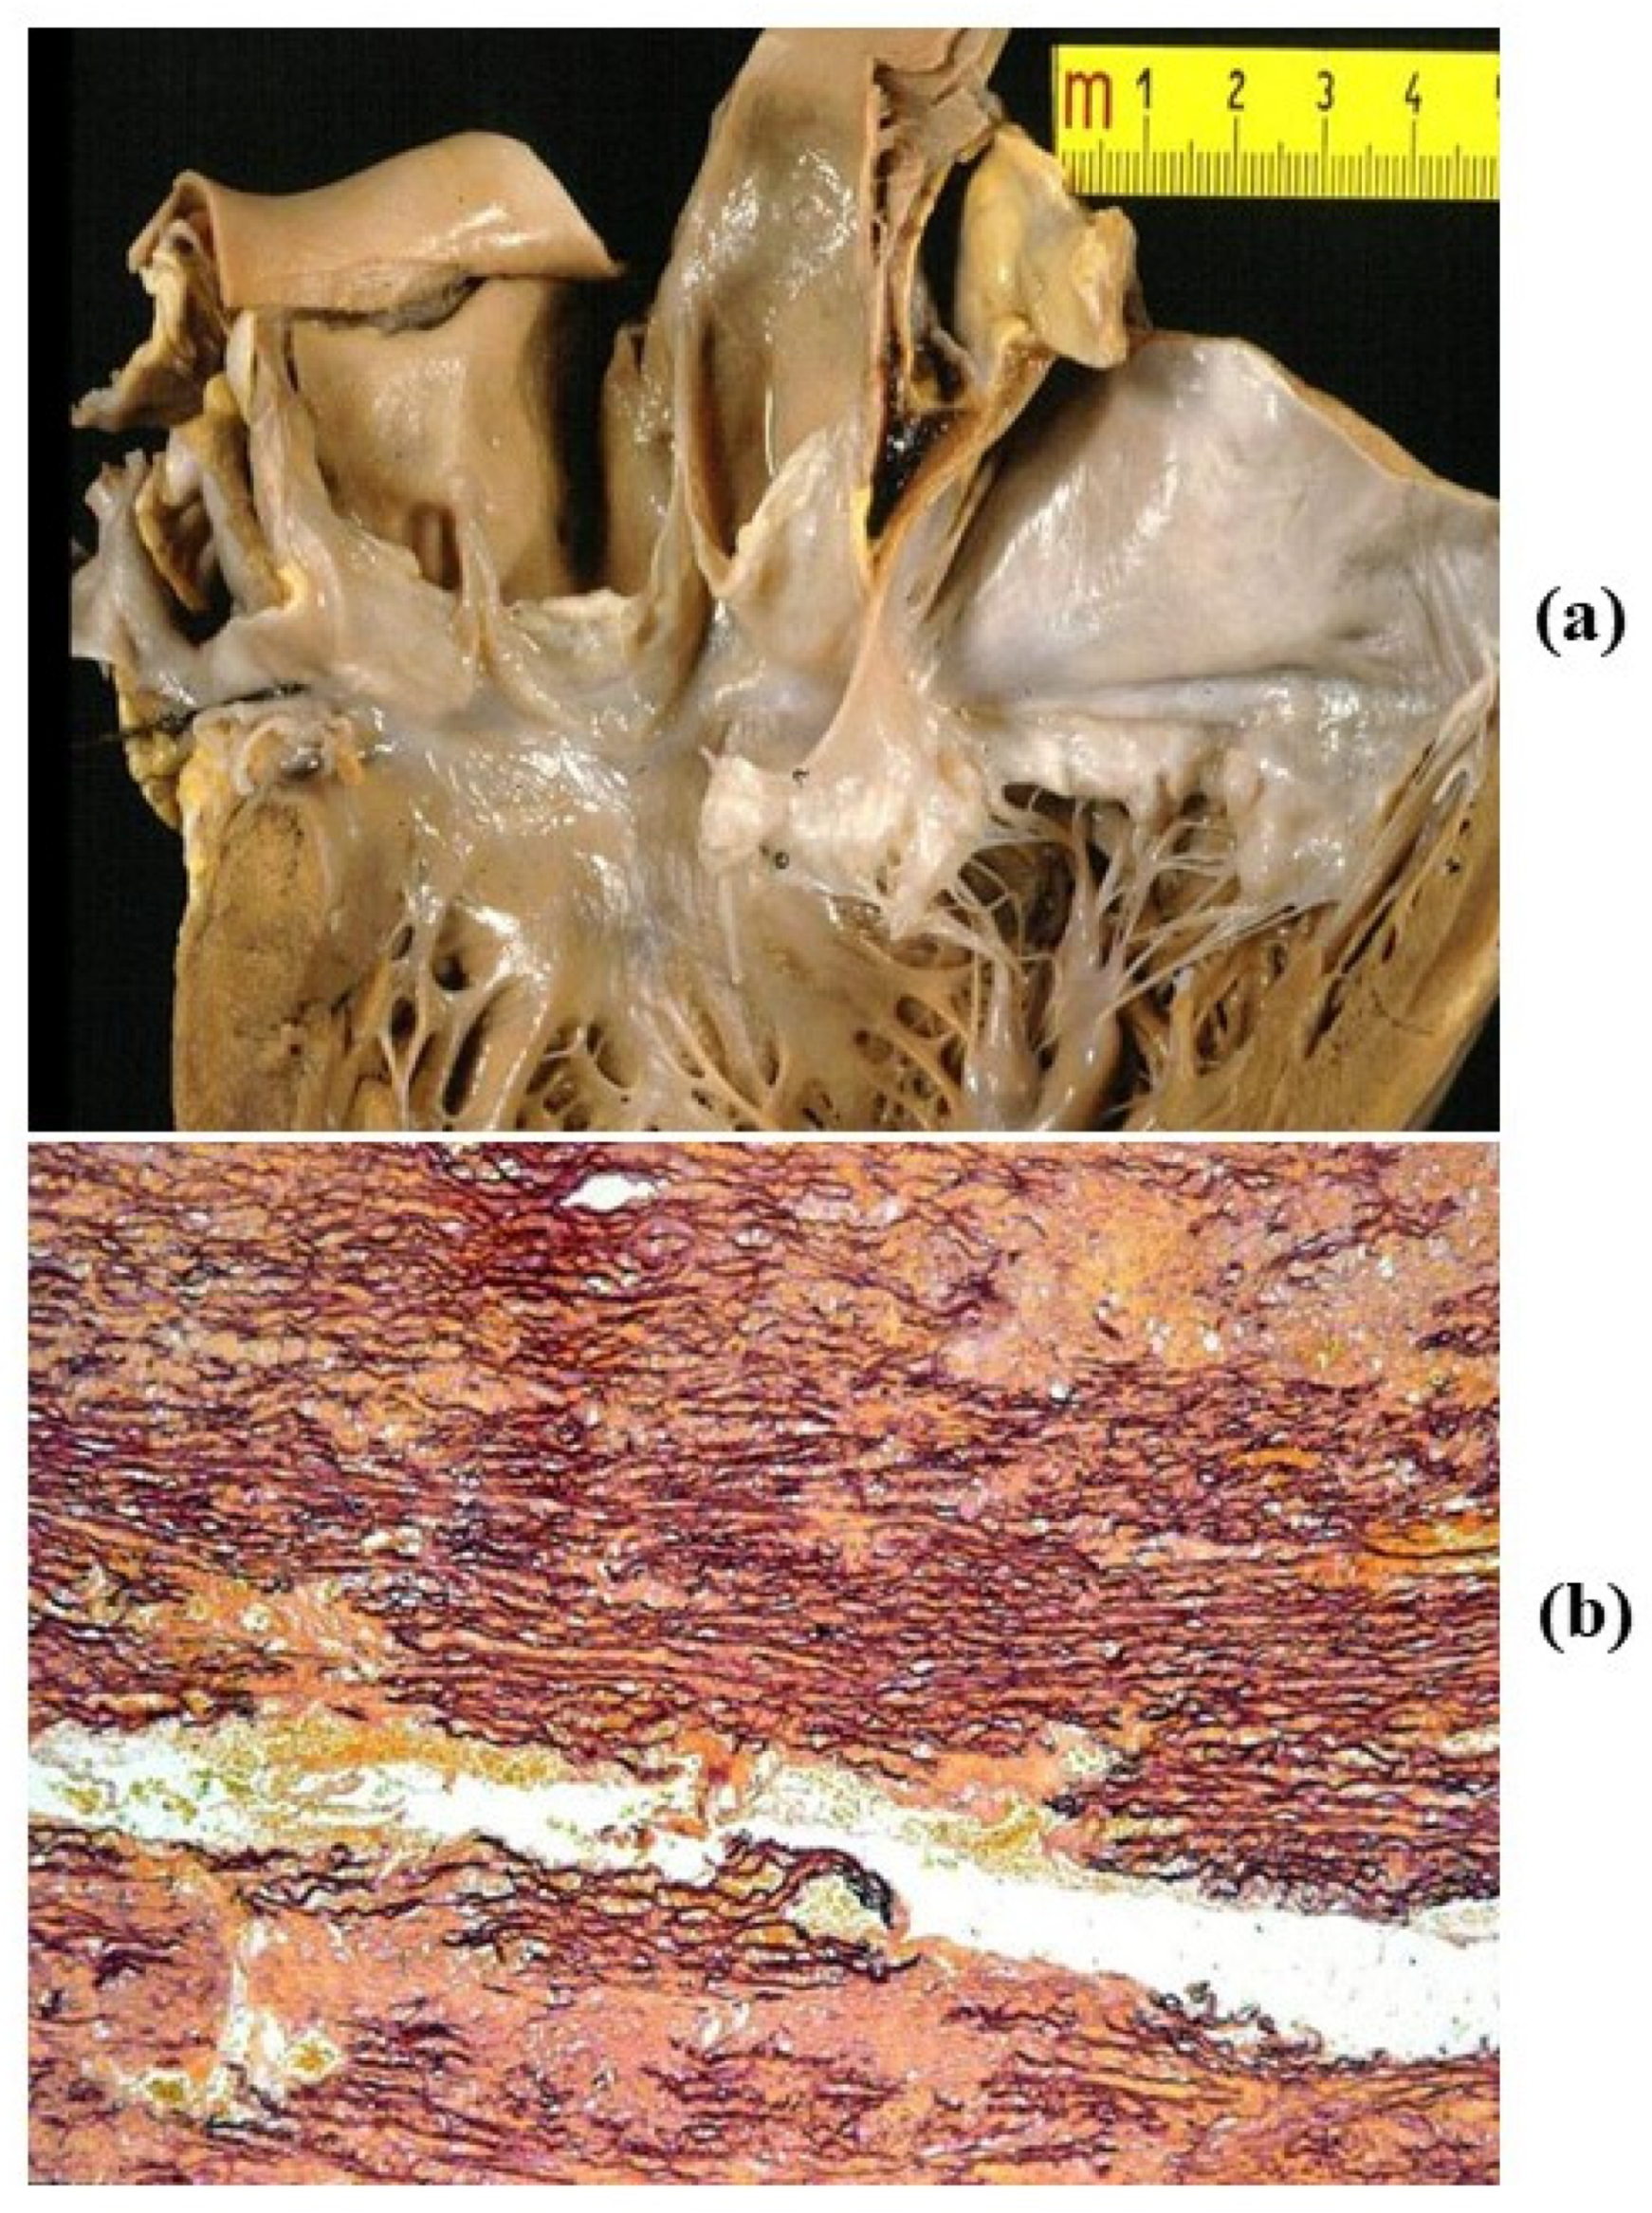

- Cellular repopulation was observed in the outer part of implanted homograft wall by novel smooth muscle cells in the lamellar units (Figure 32a,b) and in the intima with a novel myointimal layer; this layer was noticed also in small animals such as rodents [68]. Novel endothelial cells appeared to line both the aortic wall intima and inflow/outflow at the cusp surface, as well as vasa vasorum, and valve spongiosa appeared repopulated by interstitial cells (Figure 32c,d);

- Cell density, when compared to non-decellularized control allografts, showed 20% repopulation both in the aortic wall and at the cusp level (Figure 34);

- Mean calcium content by spectroscopy in aortic homografts at 14 months from implant was scanty: 4.24 ± 2.17 mg/g dry weight in the wall vs. 0.530 in controls and 5505 ± 2.04 in the cusps vs. 0.936 in the controls.